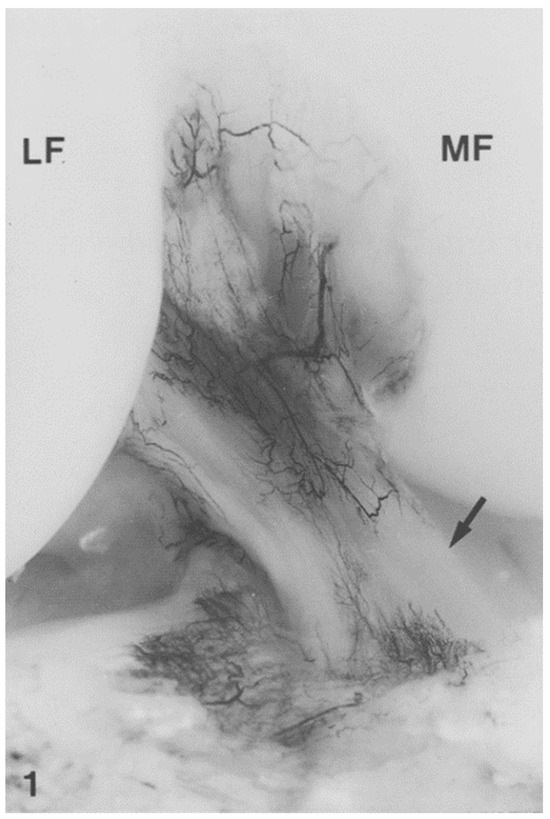

7. Regional ACL Histological Differences and Complexities

- Murray, M.M.; Spector, M. Fibroblast distribution in the anteromedial bundle of the human anterior cruciate ligament: The presence of alpha-smooth muscle actin-positive cells. J. Orthop. Res. 1999, 17, 18–27. [Google Scholar] [CrossRef]

- Weiss, M.; Unterhauser, F.N.; Weiler, A. Crimp frequency is strongly correlated to myofibroblast density in the human anterior cruciate ligament and its autologous tendon grafts. Knee Surg. Sports Traumatol. Arthrosc. 2012, 20, 889–895. [Google Scholar] [CrossRef] [PubMed]

- Zhao, L.; Thambyah, A.; Broom, N.D. A multi-scale structural study of the porcine anterior cruciate ligament tibial enthesis. J. Anat. 2014, 224, 624–633. [Google Scholar] [CrossRef]

- Zhao, L.; Lee, P.V.S.; Ackland, D.C.; Broom, N.D.; Thambyah, A. Microstructure Variations in the Soft-Hard Tissue Junction of the Human Anterior Cruciate Ligament. Anat. Rec. 2017, 300, 1547–1559. [Google Scholar] [CrossRef]